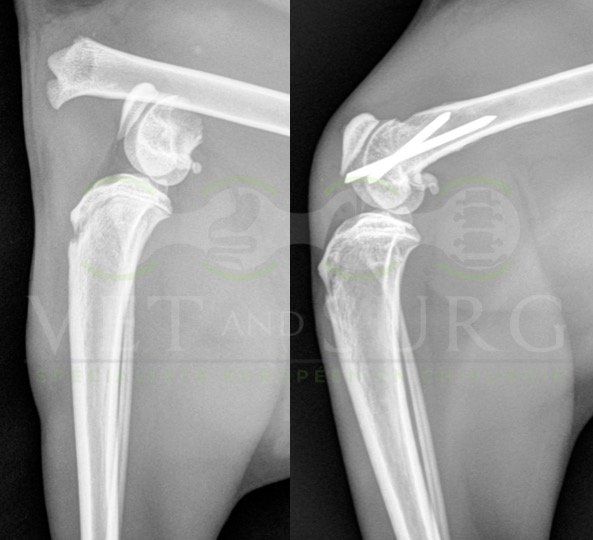

Fracture Salter-Harris sur un chaton Européen de 10 mois

Spike, chaton européen mâle de 10 mois, a été présenté en consultation pour boiterie du membre postérieur droit à la suite d'une chute depuis le 1er étage.

A la radiographie, une fracture de type Salter-harris 1 est diagnostiquée, avec déplacement de l'about discal.

Une réduction de la fracture par pose de 2 broches en croix a été réalisée.